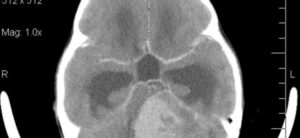

Медуллобластома: что это такое, симптомы, лечение, прогноз

Что такое медуллобластомы? Медуллобластома — наиболее частая злокачественная опухоль головного мозга у детей. Медуллобластомы по определению возникают в мозжечке, части головного мозга у основания черепа, чуть выше ствола мозга. Мозжечок участвует во многих функциях, включая координацию произвольных движений (например, ходьба, мелкая моторика) и регуляцию равновесия и позы. Медуллобластомы возникают из примитивных, неразвитых клеток головного мозга. …